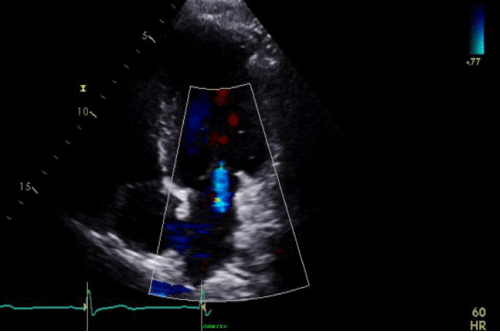

Echocardiogram: Increased LV cavity size, mitral annular dilation with severe functional mitral regurgitation. LVEF = 35% (Figure 10).

TTE apical 4-chamber view revealing annular dilation with severe central MR